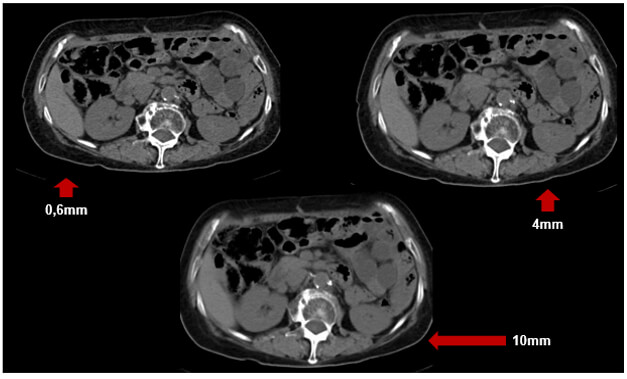

SR and Slice Thickness

Remember, a high spatial resolution is important for one to discriminate between structures that are located within proximity to each other.

The thickness of the slice also impacts spatial resolution. As shown in these two images, when the slice thickness is larger the spatial resolution is lower. The thicker the slices the less the detail in the image. Large slice thicknesses reduce spatial resolution in the cranial-caudal axis; they also reduce the sharpness of edges of structures in the transaxial image.